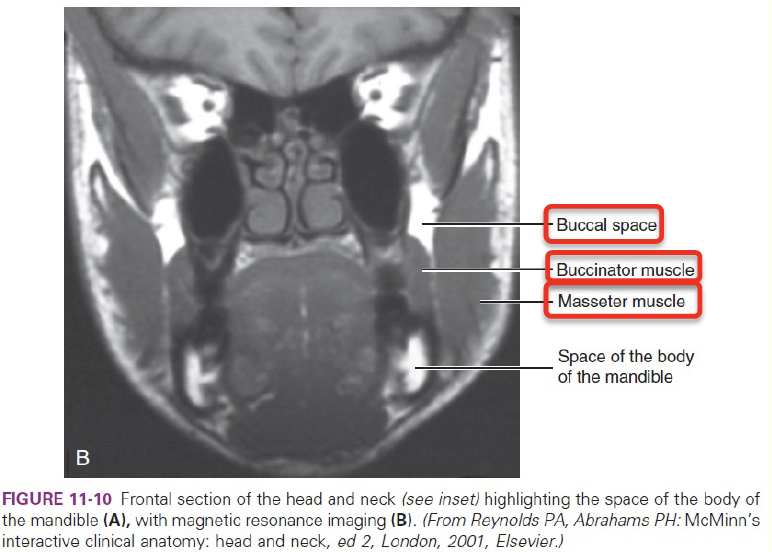

Buccal space

- Buccal fat pad

- Parotid duct

- Facial a.